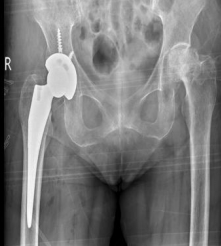

▲患者术前影像学检查

于是在朋友的建议下来到了

昆山市中医医院关节骨科

图片

尹自飞副主任医师接诊了黄阿嬷

经过查体及完善术前检查后

决定为阿嬷行髋关节置换术

▲患者术后影像学检查

术后阿嬷恢复良好

术后第二天下地行走

一周康复出院!